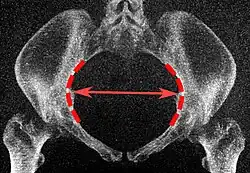

Diameters of superior aperture of lesser pelvis (female)

The diameters or conjugates of the pelvis are measured at the pelvic inlet and outlet and as oblique diameters.

Name Description Average measurement in female

Anteroposterior or conjugate diameter or conjugata vera Extends from the upper margin of the pubic symphysis to the sacrococcygeal joint; about 110 mm.

Transverse diameter Extends across the greatest width of the superior aperture, from the middle of the brim on one side to the same point on the opposite; about 135 mm.

Oblique diameter Extends from the iliopectineal eminence of one side to the sacroiliac articulation of the opposite side; about 125 mm.

Anatomical conjugate Extends from the pubic symphysis to the promontory; about 120 mm.

Diagonal conjugate Extends from lower margin of the pubic symphysis to the sacral promontory; about 130 mm.

Straight conjugate Extends from the lower border of the pubic symphysis to the tip of coccyx. The coccyx can bend posteriorly and expand the diameter with 25 mm; about 95 mm (+ 25 mm).

Median conjugate Extends from the lower border of the pubic symphysis to the lower border of the sacrum; about 115 mm.